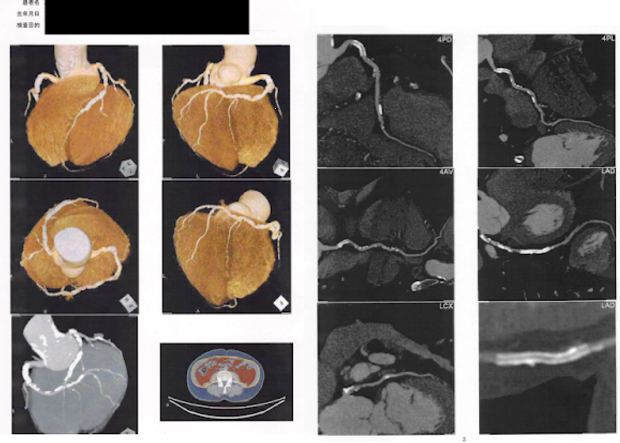

2020.10.9 半年後のCT画像

2020年の初めごろから、寒い朝などに時々、歩きはじめると胸が苦しく、胸を押さえ付けられるような違和感を感じるようになっていた。違和感はすぐに消失していた。コレステロールは若い時から高かった。父か母から遺伝子をもらったようだ。そんな状況が1,2か月続いた。改善なく、胸痛かなと認識するようなった。そのことを3月の始め、Y医師との meetingの後、「自分のことなんだけど、最近、時々胸が痛い、恋の病かな・・」と切り出した。すぐに循環内科のS医師に連絡してくれて、その日のうちに心電図を測ってもらい、翌日、負荷心電図、24時間ホルダー心電図計を付けて帰宅した。労作性狭心症と診断され、冠動脈CT検査をしたのがその週末で、翌週にはその結果と紹介状を持ってM記念病院を受診。週明け、3月後半の仕事のリスケジュールを行い、24日(水)に心臓カテーテル検査のため入院。その翌週の30日再入院して翌日、左前下降枝にステントを挿入。もう1か所(右冠動脈)は、コロナ禍のため、待機手術となり、6月23日に施行。これも無事済み、その後、食事、運動に留意しながら、投薬と定期的な検査フォローを続けてきた。

今年2月、自覚症状はないものの、心電図所見で虚血疑い(?)を指摘され、冠動脈CT検査に加えて、心臓MRI検査を実施した。もう1回ステント挿入かと半分覚悟し、しばらく気持ちが落ち込んだ。

結果:中等度(以上)の狭窄を認める箇所はあるものの、ストレス時、安静時ともに、明かな血流の欠損( Perfusion defect )を認めなかったため、今回はこれまで通り食事、運動、投薬で経過観察となった。リスクを抱えながらではあるが、とりあえずホッとしたのは今週のはじめ。